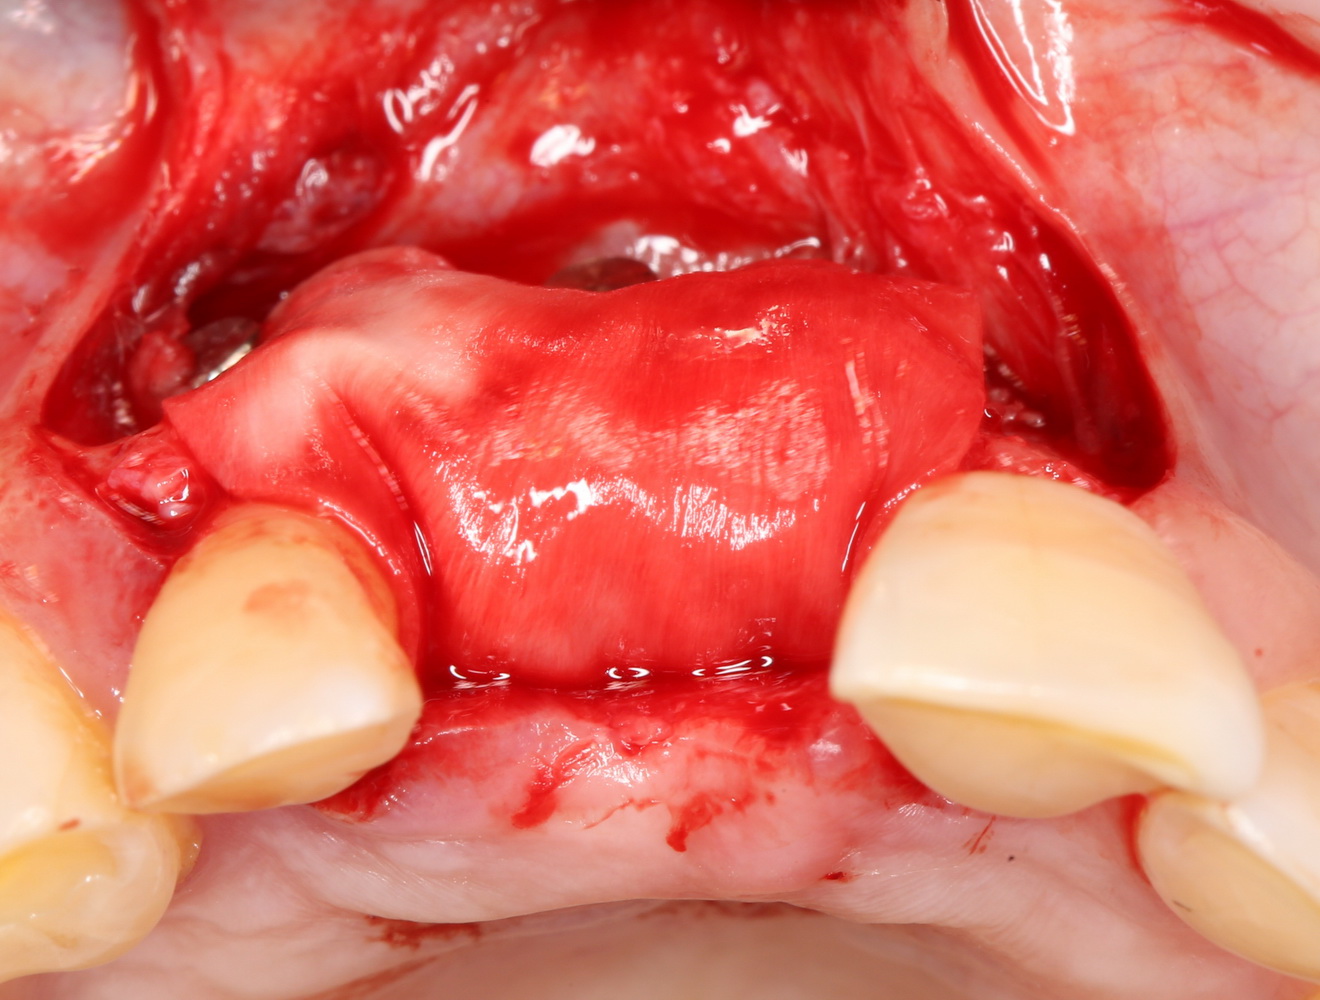

Затем укладывается и конфигурируется аутокостная стружка:

Если после этого BioGide намочить физраствором, им легко укрыть получившийся объем:

Для надежности можно зафиксировать пинами:

Ну и, швы: